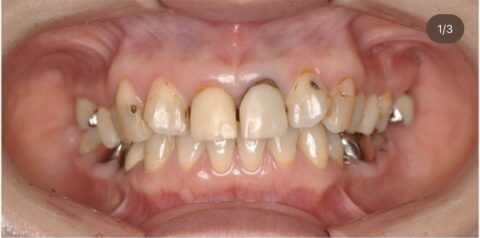

さて本日は無痛リラクゼーション治療で前歯と奥歯を同時に治療をしたケースのご紹介です。

▶︎前歯6本 ジルコニアセラミックプレミアム

▶︎奥歯4本 ジルコニアクラウンファイン

▶︎費用 前歯¥220,000-/本 奥歯¥187,000-/本

寝ている間に全て治療が終わる事により歯科恐怖症かつ大掛かりなケースでも最後まで治療を終える事ができました。

また、白い綺麗な歯並びを獲得したことにより綺麗な口元を獲得できています。